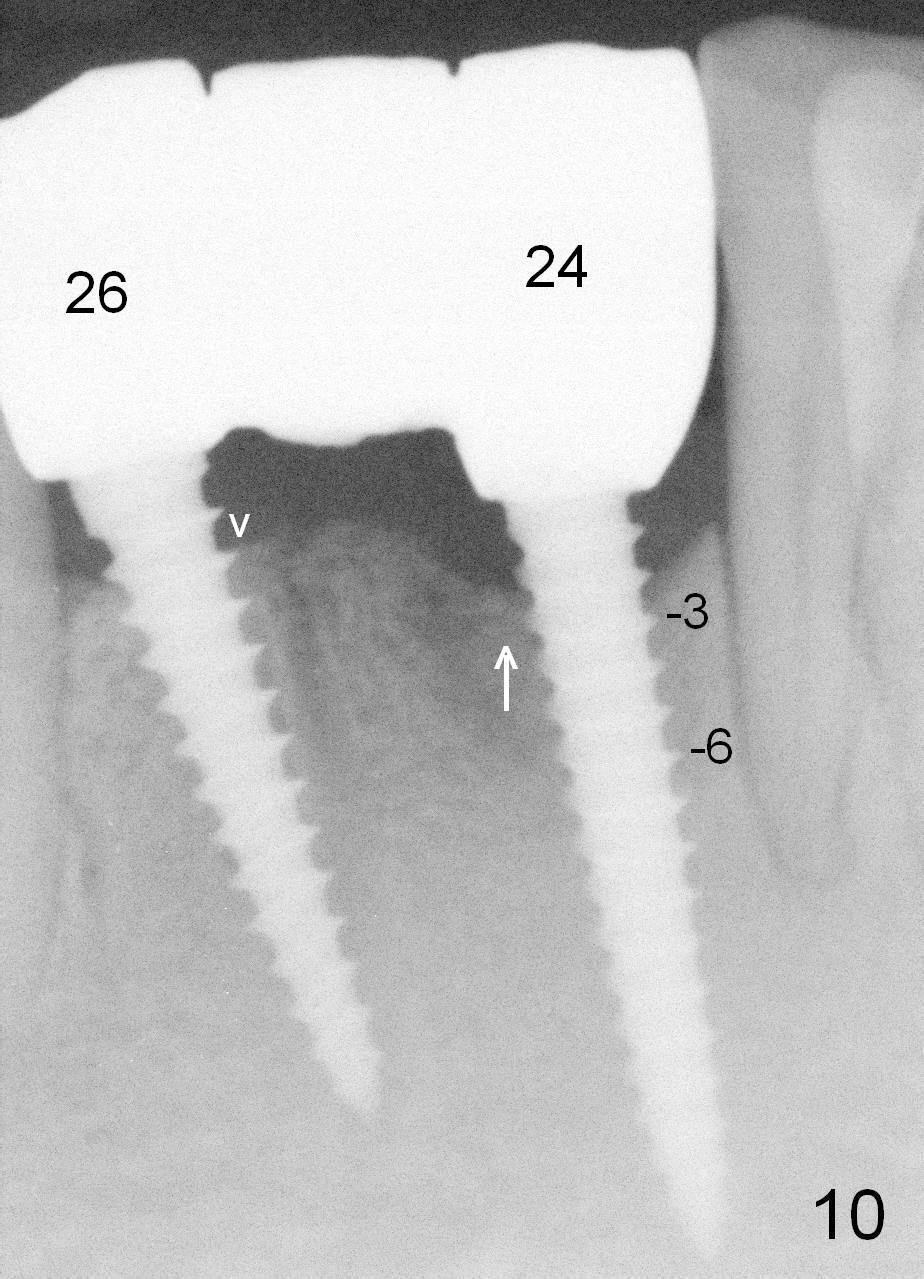

Fig.7 shows these two one piece implants immediately prior to cementation of the FPD (Fig.8). They are much more parallel to each other after prep, as compared to Fig.6. Fig.9 shows apparent bone growth around #24 implant (at the crest) 6,9 months post cementation and surgery, respectively. Orthodontic treatment will incorporate the fixed partial denture. Fig.10 shows that bone grows coronally (arrow) to cover 3 threads (from #6 thread to #3) at the site of #24 one year after functioning. There is mild buccal gingival infection involving #26 retainer. Preop CBCT is reviewed to determine whether it is related to potential thread exposure. It appears that at the sites of #24 (Fig.13,14) and 26 (Fig.11,12), 2.5 mm implant is more appropriate for the narrow ridge than 3.0 mm one. In fact, periimplantitis develops at #26 two years of absence of perio maintenance (because of atrial fibrillation with blood thinner; Fig.15, 3 years 7 months post cementation). Periimplantitis persists 4.5 months later. Although water pik is purchased, it is not used often because of low blowing force. If needed, remove the FPD atraumatically. Unwind the implant, clean the coronal threads with Titanium brush or remove the exposed threads and replant the implant with bone graft.